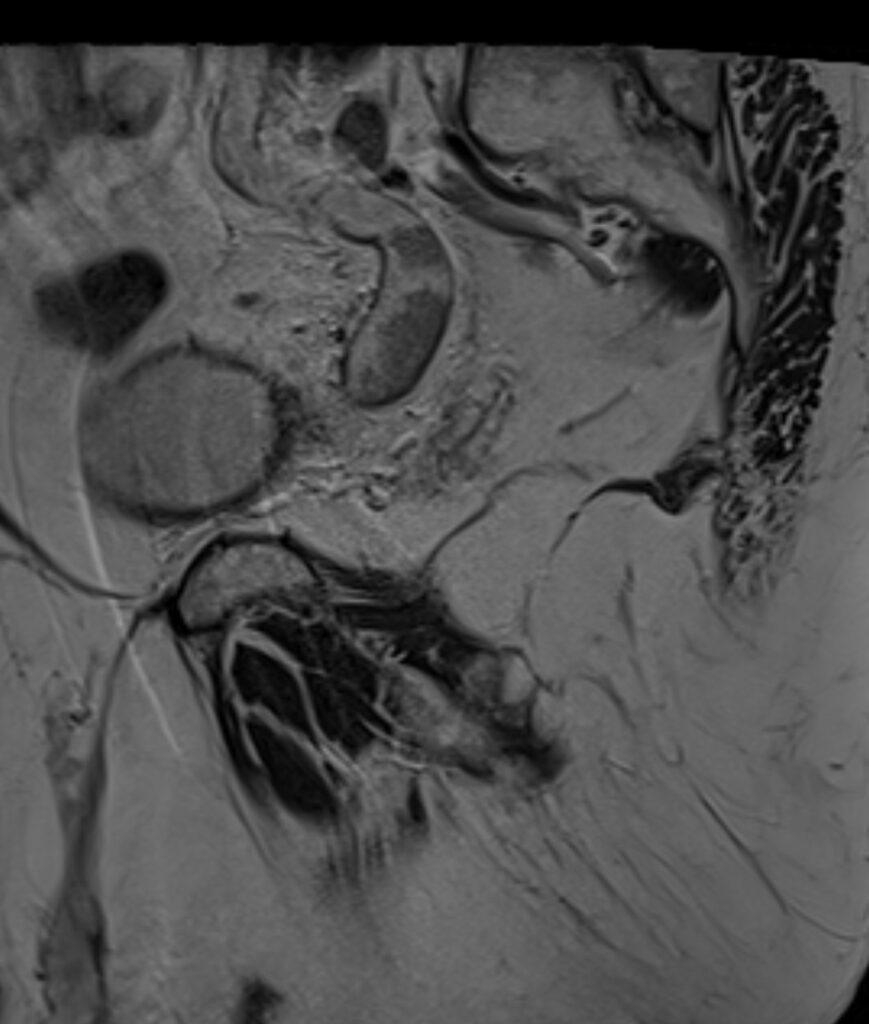

*69-year-old male with haematuria and left flank pain.

Answer: Transitional cell carcinoma (TCC) of the ureter

MR images revealed the left dilated ureter and intraluminal polypoidal masses at its distal segment. Associated moderate left hydronephrosis is noted.

TCC of the ureter are rare compared to similar tumors elsewhere along the urinary tract. It accounts for only 1% of all upper urinary tract malignancies.

Location; proximal third: 3%, mid third: 24%, distal third: 73%